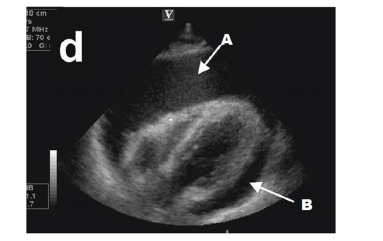

O ecocardiograma à beira leito (ECO) pode ser muito útil na sala de emergência, durante a parada cardiorrespiratória (PCR) ou na fase da perirressuscitação, sendo que o uso do ECO na avaliação inicial de pacientes com hipotensão aumenta o potencial e a rapidez de percepção entre possíveis diagnósticos diferenciais, podendo auxiliar na escolha terapêutica mais adequada e, assim, resultar em melhores resultados. O ECO já é considerado classe I para avaliação de pacientes que desenvolvem ou persistem com instabilidade hemodinâmica, e o último guideline da American Heart Association colocou o ECO como classe IIb, para avaliação inicial dos pacientes com PCR.

A figura a seguir representa qual provável etiologia para justificar uma PCR?

enunciado 1256698-1